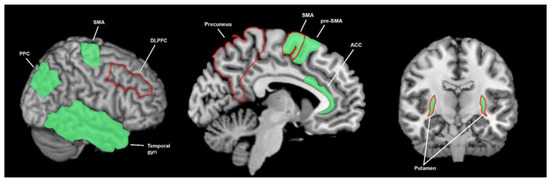

3.3. What Brain Areas Are Involved in Sensory Processing?

3.3.1. What Brain Areas Are Involved in Temporal Processing in Healthy Cohorts?

3.3.2. What Brain Areas Are Found to Function Abnormally in Temporal Processing in People with Parkinson’s Disease?

3.3.3. What Brain Areas Are Involved in Auditory Processing in Healthy Cohorts?

3.3.4. What Brain Areas Are Found to Function Abnormally during Auditory Processing in Patients with Parkinson’s Disease?

3.3.5. What Brain Areas Are Involved in Visual Processing in Healthy Cohorts?

3.3.6. What Brain Areas Are Found to Function Abnormally during Visual Processing in People with Parkinson’s Disease?

3.3.7. What Brain Areas Are Involved in Tactile Processing in Healthy Cohorts?

3.3.8. What Brain Areas Are Found to Function Abnormally during Tactile Processing in Patients with Parkinson’s Disease?

3.3.9. What Brain Areas Are Involved in Proprioceptive Processing in Healthy Cohorts?

3.3.10. What Brain Areas Are Found to Function Abnormally during Proprioceptive Processing in Patients with Parkinson’s Disease?

3.4. The Breadth of Sensory Response and Multisensory Response of the Basal Ganglia